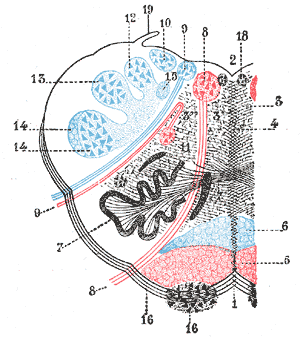

| |

| Medulla oblongata, shown by a transverse section passing through the middle of the olive. (Lateral medullary syndrome can affect structures in upper left: #9, #10, #12, #13, #14 and #19.) | |